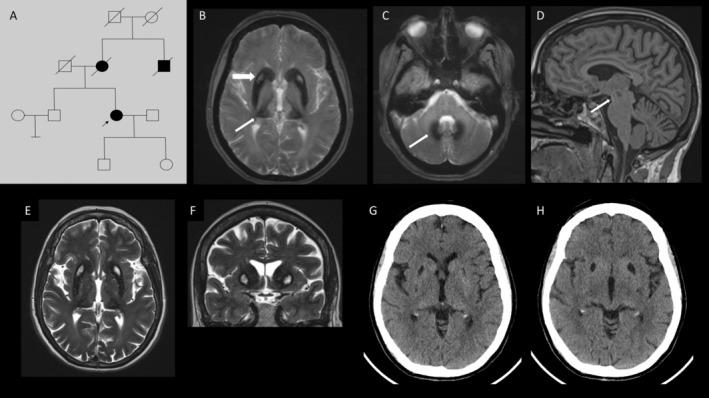

Aceruloplasminemia: Unique Clinical and MRI Findings in a Patient with a Novel Frameshift Mutation.

https://cdn.ncbi.nlm.nih.gov/pmc/blobs/1acc/11322588/e32d1b014825/MDC3-11-S14-g001.jpg